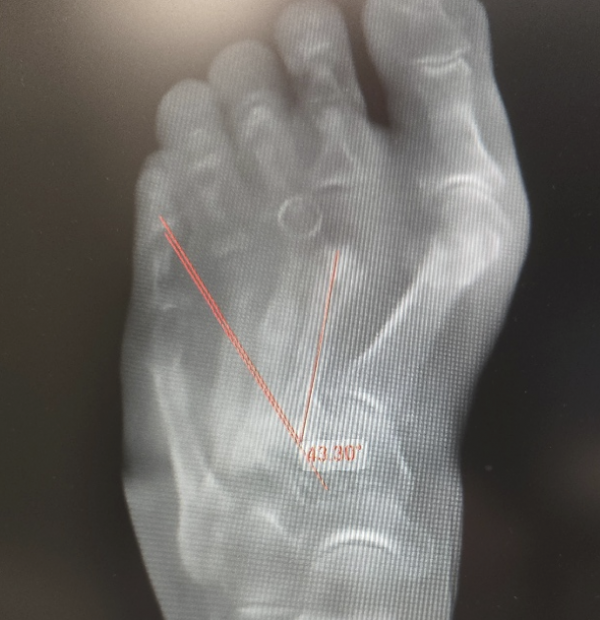

In unserer Praxis nutzen wir bevorzugt den Engel-Winkel — eine Methode, die 1983 von Engel, Erlick und Krems beschrieben wurde und sich seither in der klinischen Praxis bewährt hat [Engel et al., J Am Podiatry Assoc, 1983]. Der Engel-Winkel misst den Winkel zwischen der Längsachse des zweiten Mittelfußknochens und der Längsachse des zweiten Keilbeins auf der belasteten Röntgenaufnahme. Er ist schnell zu bestimmen, gut reproduzierbar und für die klinische Entscheidungsfindung ausreichend genau.

Als Normwert gilt ein Engel-Winkel von unter 25 Grad. Darüber liegt definitionsgemäß ein Sichelfuß vor — je größer der Winkel, desto ausgeprägter die Fehlstellung.

Experten-Tipp: wenn die Längsachse des zweiten Keilbeins (os cuneiforme intermedius) lateral des vierten Mittelfußköpfchens verläuft, liegt fast immer ein erheblicher Sichelfuß vor.